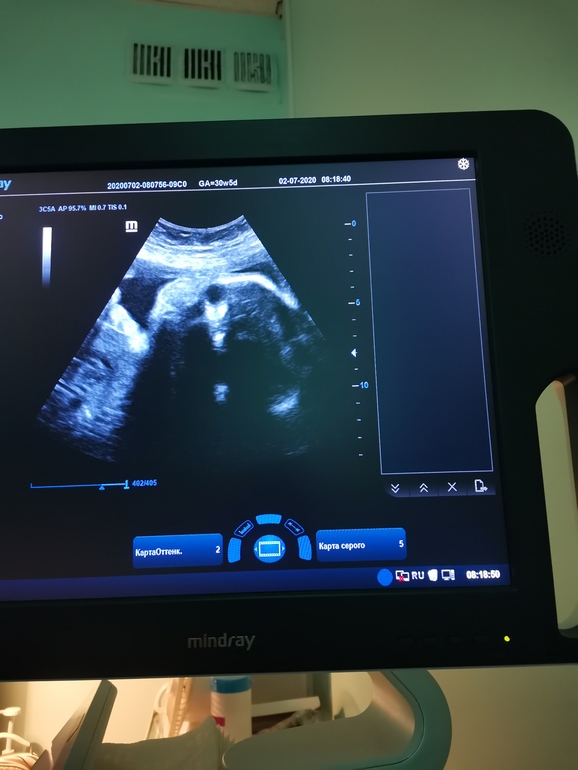

Третий скрининг ✅30/5

Сегодня прошла третий скрининг, все хорошо, мылыш весит 1650

Все параметры на 30/31 неделю, а вот голова на 32/33 недели. Надеюсь ничего страшного? 🤔Врач узи ничего страшного не сказала

Рубец 2 мм, говорит не из самых толстых, но признаков истончения нет.